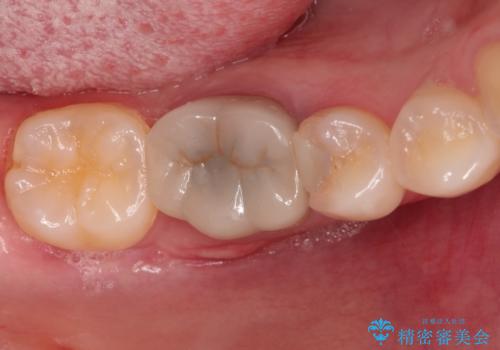

- 右下の奥歯の調子がよくないとのことで来院されました。

レントゲン・口腔内診査をお行い、保存が難しいことがわかりました。

抜歯後インプラントをする計画としました。

見た目では問題がなさそうでも、レントゲン撮影・診査を行うと状態が悪くなっていることがあります。